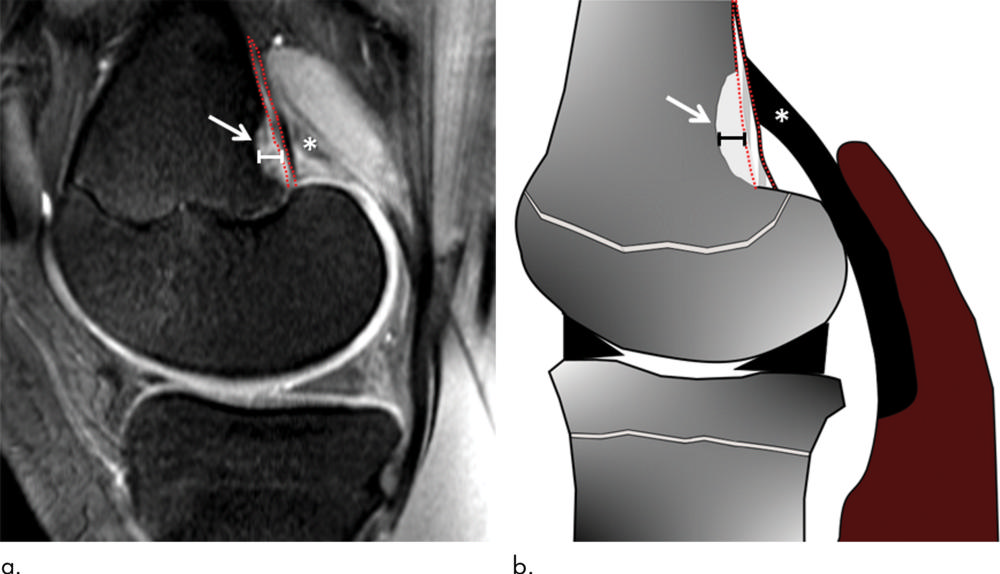

Figure 1. (a) Sagittal fat-suppressed proton density–weighted MRI scan in a 14-year-old male control participant with distal femoral cortical irregularity (DFCI) (arrow) at the level of the tendon attachment of the medial head of the gastrocnemius muscle (MHG) (*). (b) Sagittal illustration with DFCI (arrow) at the MHG attachment (*). The size of the DFCI is determined as the greatest anteroposterior diameter (solid line in a and b). Note that the bandlike hyperintense periosteal stratum osteogenicum (in between red dotted lines in a and b) is not included in the measurement.